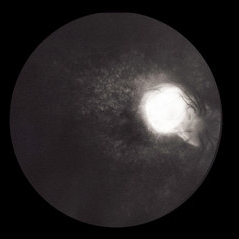

Ocular Toxocariasis slide 1

Ocular Toxocariasis slide 1

Oct 22 2012 by Ronald C. Gentile, MD

8-year-old boy with a history of puppy exposure failed his school screening in the right eye. Fundus examination revealed a old scarred granuloma involving the macula. Serum testing for anti-Toxocara antibodies were positive.

Photographer: The New York Eye & Ear Infirmary Department of Medical Imaging

Condition/keywords: scarred granuloma, toxocariasis